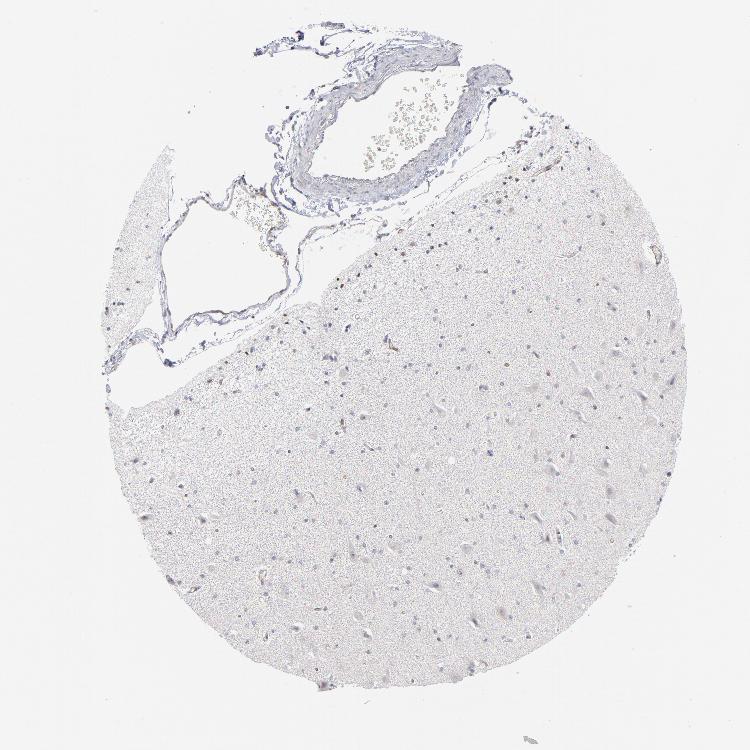

HIPPOCAMPUS - Antibody stainingi

Antibody staining in the annotated cell types in the current human tissue is reported as not detected, low, medium, or high, based on conventional immunohistochemistry profiling in selected tissues. This score is based on the combination of the staining intensity and fraction of stained cells.

Each image is clickable and will lead to virtual microscopy that enables deeper exploration of all samples and also displays staining intensity scores, fraction scores and subcellular localization as well as patient and tissue information for each sample.

Antibody HPA001429Antibody CAB003836Antibody CAB080233

Glial cells Not detectedNot detectedNot detected

Neuronal cells LowNot detectedLow